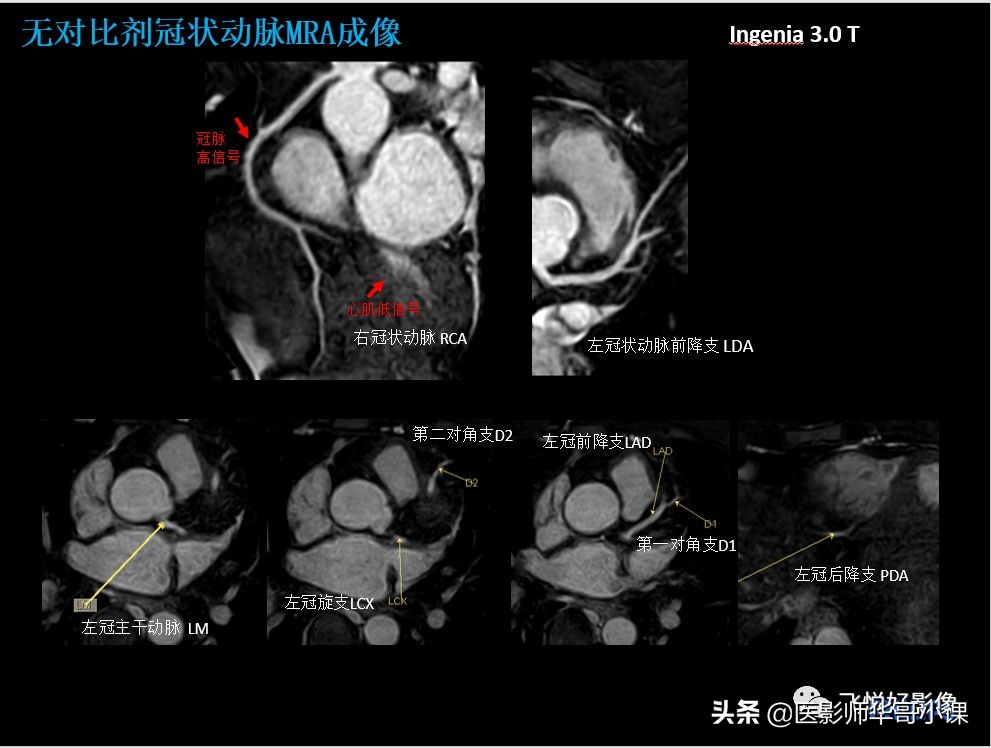

本期内容为无对比剂冠状动脉MRA、CMR心梗病例。飞利浦独特的极速冠状动脉MRA技术快至两分钟便可得到高质量的冠脉图像。